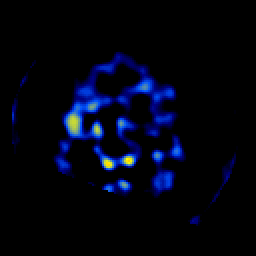

SPECT TL Study #6 -- Slice #49

[Home][Help][Clinical][Tour 1][Tour 2][Tour 3] Slice 49